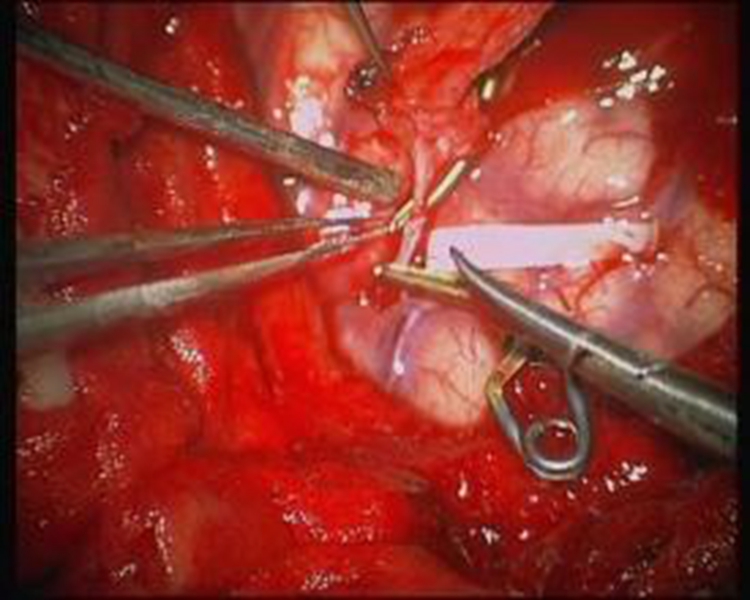

A:煙霧病目前有兩種手術方式,分別是血管搭橋手術和血管貼敷手術。血管搭橋手術是將顳淺動脈進行剝離,然後與大腦中動脈進行吻合搭橋。而血管貼敷手術是將顳淺動脈剝離後貼敷到腦的表面上。通過這兩種手術方式,主要的起到的作用是建立新的側枝循環,從而供應腦……

A:煙霧病的主要手術方式是進行顳淺動脈搭橋手術或者貼敷手術,這種手術是需要進行全身麻醉的,因此做完手術後需要臥床,並且密切觀察病情變化。如果術後恢復順利,那手術後兩三天就可以開始下床活動,早下地能夠起到改善下肢循環的作用,能夠預防出現下肢的深靜……